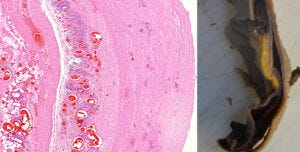

10. A crack in the wall of the aorta, lined by clusters of lymphocytes, leading to aortic rupture

On the left, a section through the wall of an aorta. This picture is taken at an even lower magnification than the one before; the lymphocytes now appear as just a cloud of tiny blue specks. To the left of this blue cloud, we see a vertical crack running through the tissue. Such a crack is also visible macroscopically in the excised specimen of an aorta shown on the right.

The aorta is the largest blood vessel of the body. It receives the highly pressurized blood ejected by the left ventricle of the heart, and it is thus exposed to intense mechanical stress. If the wall of the aorta is weakened by inflammation, as it is here, then it may crack and rupture. Aortic rupture is normally quite rare, but Prof. Burkhardt found multiple cases in his limited number of autopsies. Some of the affected aortas were also shown to have expressed the spike protein.